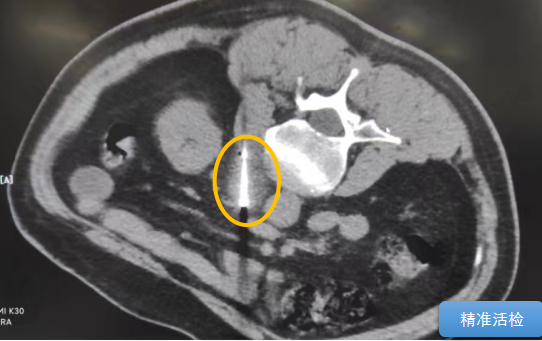

經(jīng)過多學科討論,陳寶瑩主任根據(jù)影像資料指出,患者轉(zhuǎn)移瘤位于腹膜后,內(nèi)側(cè)瀕臨人體最大的血管——主動脈;前方同樣有血管緊貼腫瘤;外側(cè)是腎臟,后方是椎體和神經(jīng),夾縫中進針難度大,治療時要避免周圍重要臟器、血管和神經(jīng)的損傷,因此可以選擇CT引導下精準穿刺活檢同步冷凍消融治療,即獲得病理組織有利于下一步全身治療方案的調(diào)整,同時殺死腹膜后轉(zhuǎn)移瘤,周圍正常組織損傷的可能性也小。

術(shù)中陳寶瑩主任、李鐵柱教授、兀云飛醫(yī)生、魏東紅技師、汝平護士協(xié)調(diào)配合,夾縫進針難度雖大,但在CT引導下逐步進針,精準到位,順利活檢取得組織,由于腫瘤較大,為了提高消融效率,平行置入兩根冷凍消融針,同時啟動冷凍消融,術(shù)中清晰觀察到冰球完全覆蓋病變,患者沒有任何不舒服,治療中還可以和醫(yī)生聊天。